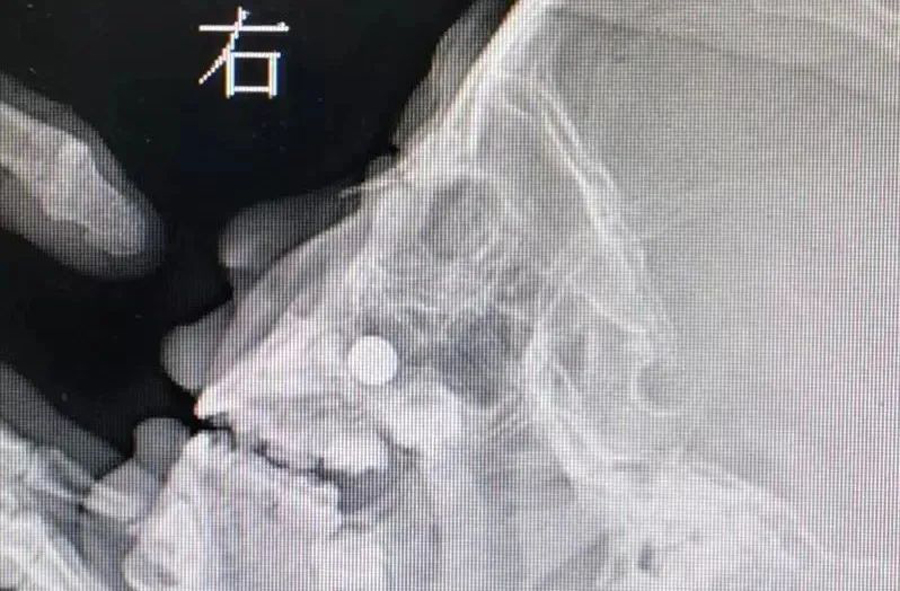

▲耳鼻喉科接诊过的鼻腔被塞进纽扣电池的案例照片